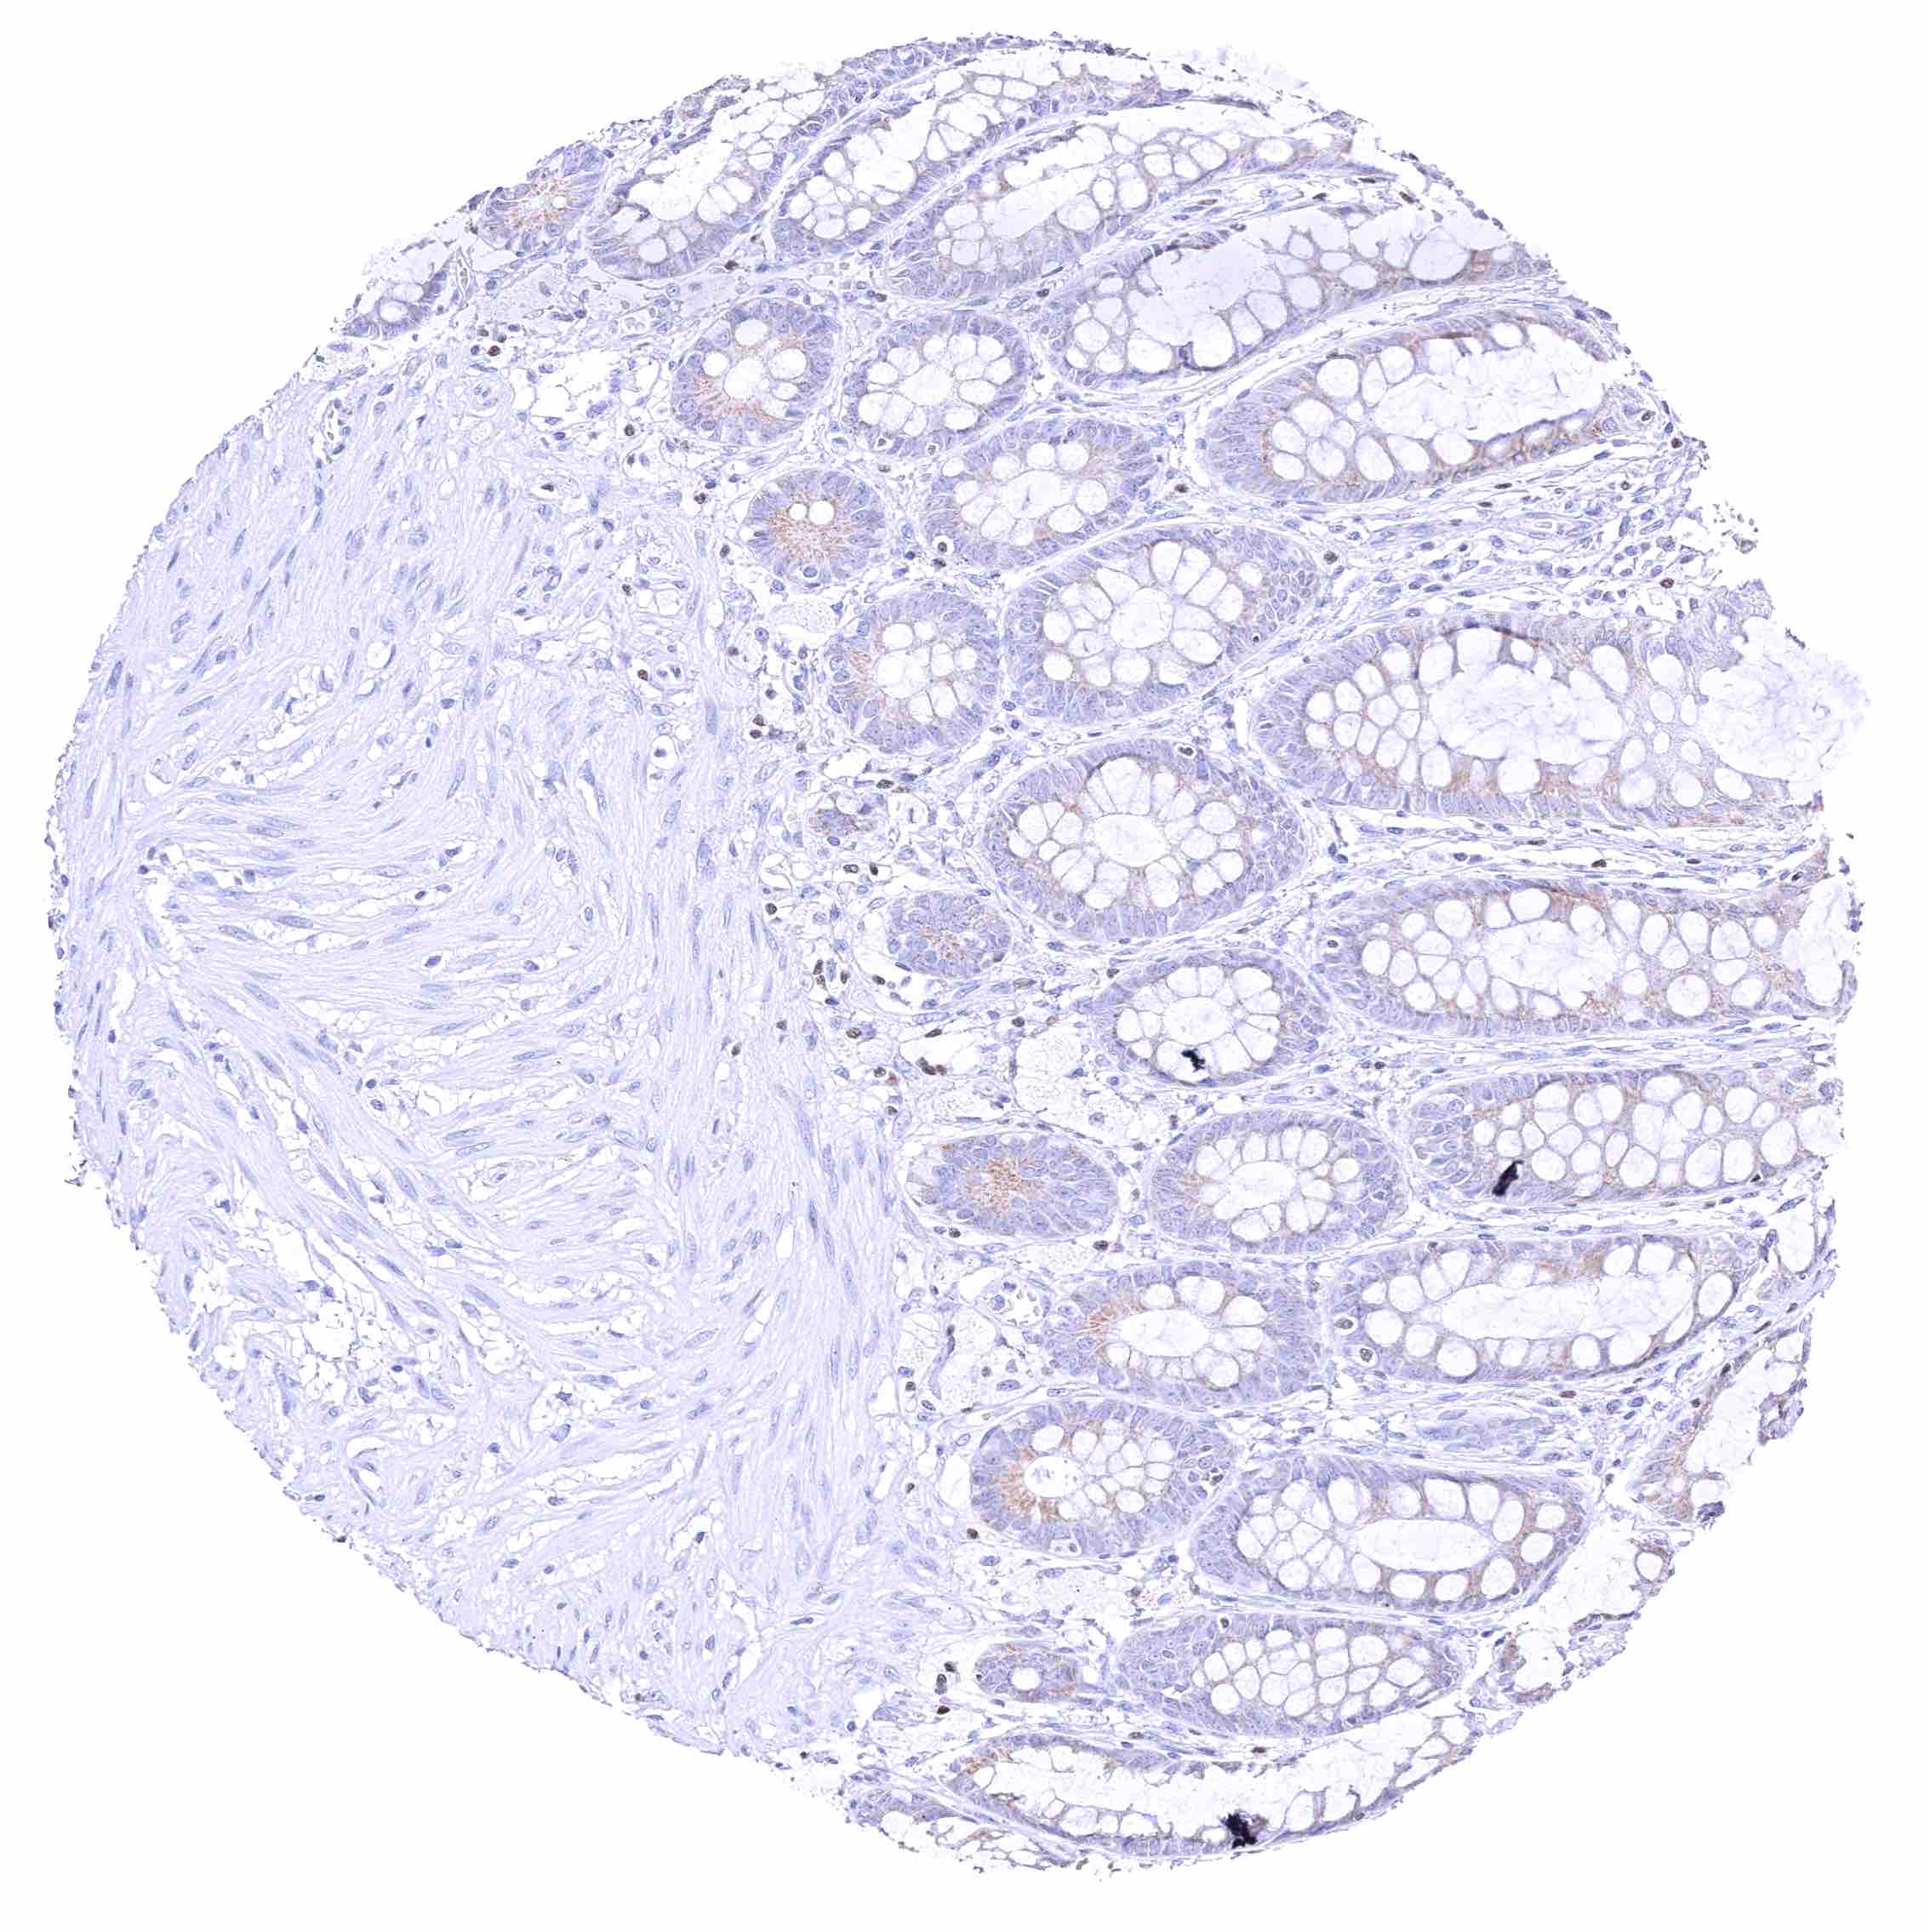

Colon descendens, mucosa – Nuclear GATA3 positivity of few lymphocytes. Faint cytoplasmic GATA3 positivity of some epithelial cells.

Colon descendens, muscular wall